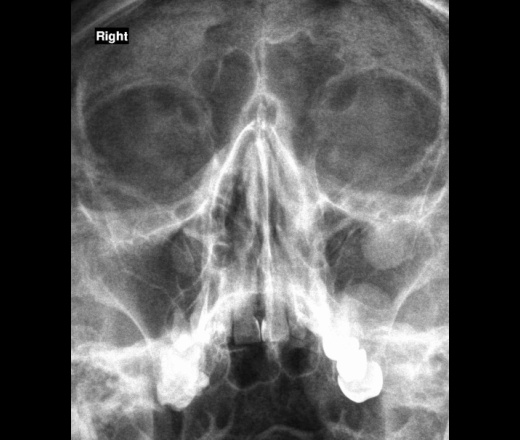

а какой вид гайморита в первом случае, полипозный?

Рентген-картина соответствует полипозному, в дальнейшем интересно будет взглянуть после лечения.

А почему в 1 случае не кисты?

А вот контроль и покажет.